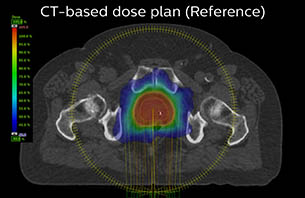

A 77-year-old male with prostate cancer cT3aN0M0, Gleason 8 and PSA 52 μg/L referred to androgen deprivation and radiation therapy with a prescribed dose of 50 Gy to the pelvic lymph node regions and 76 Gy to the prostate.

MR-only simulation workflow The 3D T1W FFE mDIXON sequence provides in-phase, water and fat images in one acquisition. Target and organs-at-risk are delineated on the 3D T2W TSE images. Prostate GTV is shown in orange, PTV in purple. The 3D bFFE sequence is used by the planner to mark the position of the fiducial markers (gold anchors) and contours are transferred to the digitally reconstructed radiographs (DRRs).

Based on the 3D T1W mDIXON images, MR-based density maps (MRCAT) are automatically generated. The VMAT (Volumetric Modulated Arc Therapy) plan is generated in TPS, based on MRCAT as primary image set. During the commissioning phase, dosimetric agreement between MRCAT-based and CT-based dose plans was studied and differences in the PTV dose were found to be minimal (<1% for most patients). Average difference in PTV mean values was 0.8% over the study group (n=62).